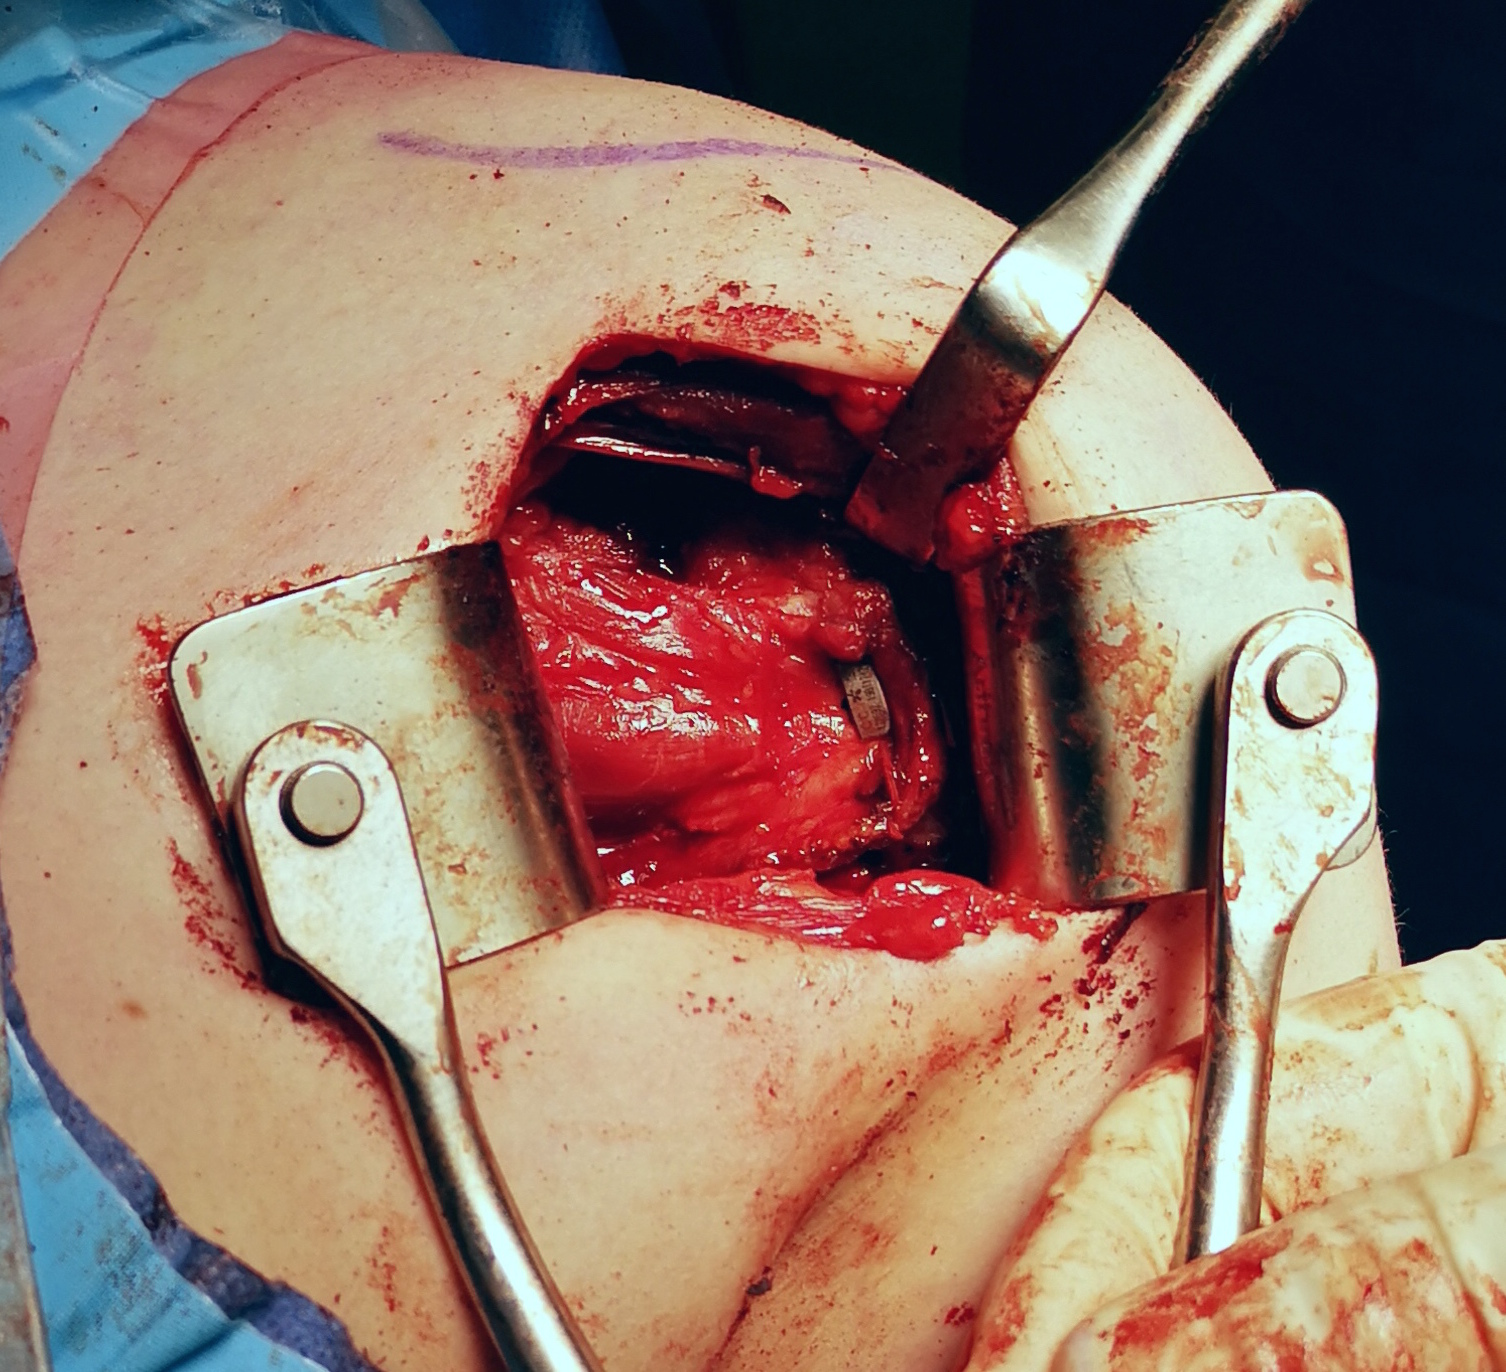

- superior advancement inferior capsular flap

- eliminate inferior pouch and reduce posterior capsular redundancy

- then suture down superior flap

- perform capsular plication / capsular shift

- +/- lateral advancement of infraspinatus